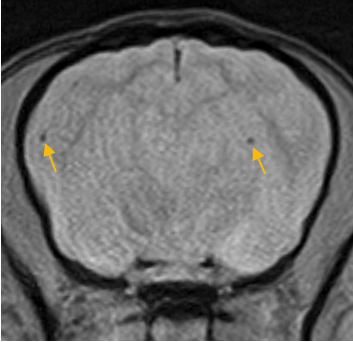

미세 뇌손상 정밀 확인(DWI)

아주 작은 손상·미세출혈 변화까지 확인에 도움됩니다.

(참고사진 : 2mm 이내의 미세 뇌출혈 환자)